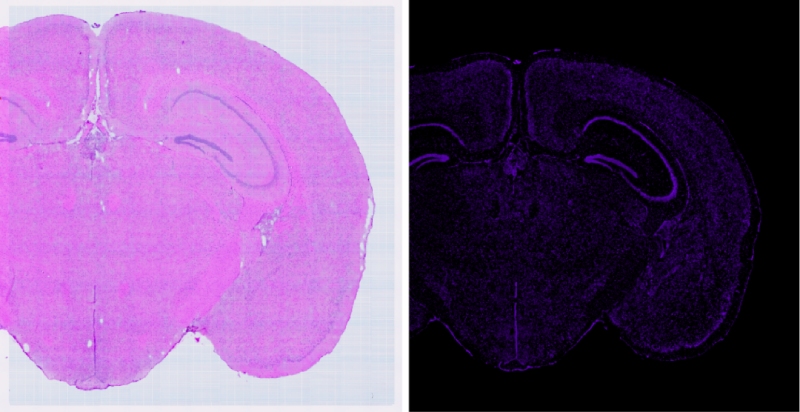

在生命科學(xué)的探索之旅中,技術(shù)的每一次革新都是我們深入理解生命奧秘的堅(jiān)實(shí)基石。百邁客生物推出顯微掃描儀領(lǐng)域的旗艦力作——BH1000掃描儀,它將引領(lǐng)我們邁入空間組學(xué)成像的新紀(jì)元。BH1000掃描儀不僅可以實(shí)現(xiàn)人體、動(dòng)物、植物以及各類玻片標(biāo)本的快速全切片掃描成像,更以其卓越的性能全面滿足百創(chuàng)空間組學(xué)實(shí)驗(yàn)的高端成像需求。其可以實(shí)現(xiàn)明場(chǎng)以及熒光的原片高清無(wú)錯(cuò)成像,結(jié)合百創(chuàng)S空間系列細(xì)胞分割算法,能夠?qū)崿F(xiàn)精準(zhǔn)的空間單細(xì)胞分割,為空間組學(xué)細(xì)胞層面的研究提供了強(qiáng)有力的支持。

通過(guò)BH1000快速(20X,8mm*8mm,小于50S)得到高清明場(chǎng)圖像與高清的熒光(支持7個(gè)熒光通道,各通道有獨(dú)立傳感器,電動(dòng)切換,標(biāo)配明場(chǎng)、?DAPI、FITC和CY3)成像結(jié)果來(lái)選擇最優(yōu)的透化時(shí)間(需要選擇熒光最亮且符合相應(yīng)明場(chǎng)結(jié)構(gòu)無(wú)明顯逸散的梯度)

可以利用BH1000對(duì)明場(chǎng)及熒光掃描過(guò)程中經(jīng)常出現(xiàn)的拼接錯(cuò)誤進(jìn)行校準(zhǔn)(自主研發(fā)BMCHiper軟件,搭配自研半透半返模塊,實(shí)現(xiàn)圖像無(wú)錯(cuò)校準(zhǔn)),得到原片無(wú)錯(cuò)高清的熒光圖像與原片無(wú)錯(cuò)高清的明場(chǎng)圖像,為后續(xù)空間數(shù)據(jù)準(zhǔn)確的定位和可視化提供基礎(chǔ),使得復(fù)雜的轉(zhuǎn)錄組數(shù)據(jù)能夠轉(zhuǎn)化為最直觀,最精準(zhǔn)的生物學(xué)見(jiàn)解。